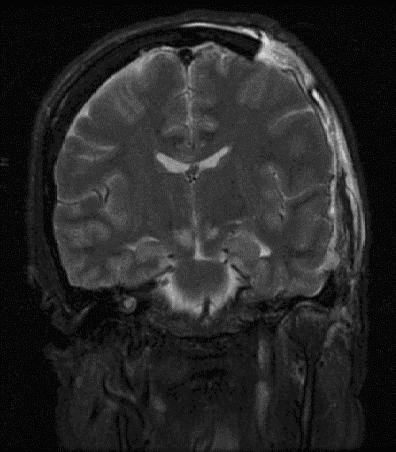

Herniation

The displacement of brain tissue as a result of a force or higher intracranial pressure is known as herniation.

The most frequent type of intracranial herniation is a subfalcine herniation.

In subfalcine herniation the brain tissue protrudes through the falx cerebri.

Uncal herniation is another type of herniation, in which the temporal lobe uncus is displaced under the tentorium cerebelli.

In an uncal herniation, compression of cranial nerve III, the oculomotor nerve, causes the ipsilateral eye to move “down and out” and the pupil to dilate.

Other potential complications of herniation include:

- Cardiopulmonary arrest occurs when the brain stem is compressed

- Infarction of the occipital lobe or the opposite homonymous hemianopia are caused by compression of the posterior cerebral artery

- Infarction occurs when the anterior cerebral artery is compressed

- Seizure(s)

- Death